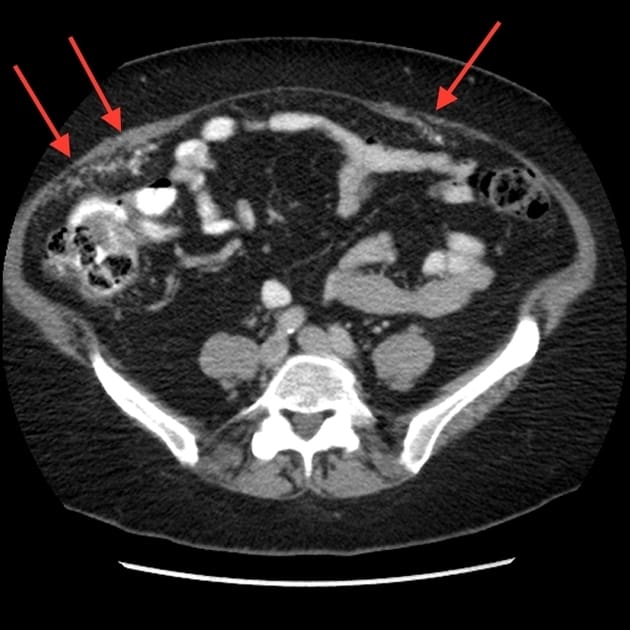

Di căn phúc mạc

» Thông tin: Nữ giới – 60 tuổi.

» Lâm sàng: Đau mạn sườn phải / Tiền sử buồng trứng.